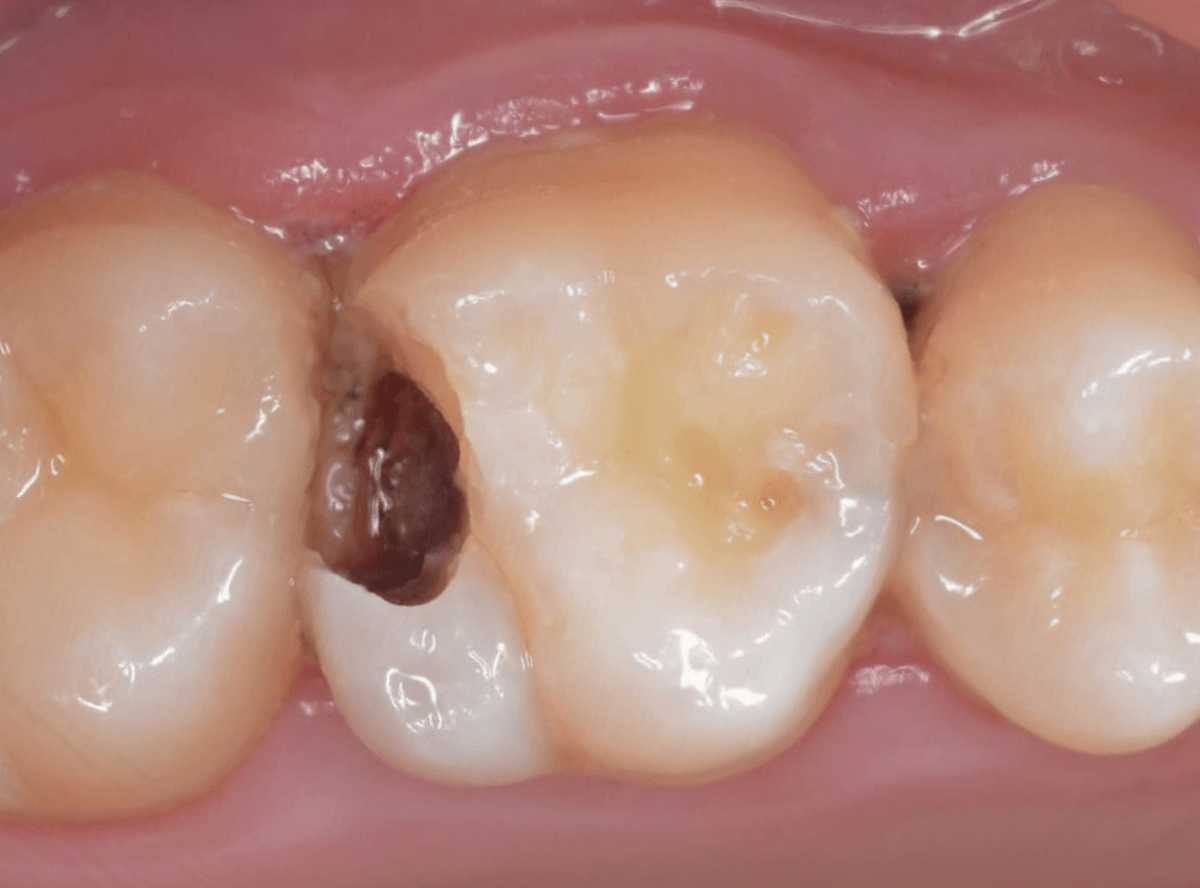

Case.21 神経に達しそうな2本の大きな虫歯

上の小臼歯の側面が明らかに虫歯になっている患者さんです。

患者さんは特に症状を感じてなさそうですが、恐らくは中で大きな虫歯になっているでしょう。

このように、自覚症状からだけでは虫歯の状況は診できません。

レントゲン写真で確認します。

青い線が歯の神経、赤い線が虫歯と思われる部分です。

2本とも、神経に達してしまいそうな大きな虫歯であると思われます。

まず、奥の歯のつめものを外してから、虫歯の治療を開始します。

手前の歯が大きな虫歯が見えてきました。

神経に達してしまいそうな虫歯ですので、ある程度削ったところで、少しずつエキスカという道具で掻き出すようにして、虫歯を除去します。

虫歯は歯を溶かして進行しますので、骨よりも固い歯もちょっと掻き出すとボロボロと崩れるようになってしまっています。

かなり虫歯を除去したところで、手前の歯は神経が顔を出してしまいました(露髄といいます)。

神経を除去する治療が必要かもしれないです。

全ての虫歯を除去したところです。

幸い、後ろの歯は薄皮一枚のところで神経まで達していない虫歯ですんでいましたが、大きな虫歯だった事には変わりありません。

いつものように、神経が痛み出さないように祈りつつ、お薬で保護して経過観察します。

虫歯は症状からだけでは判断できませんが、定期受診によって、このような大きな虫歯の処置は避けられる事がほとんどです。